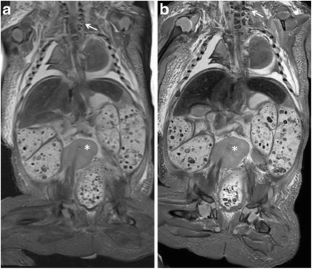

Fig. 1

Fig. 2

Fig. 3

Fig. 4

Fig. 5

Fig. 6

Fig. 7

Fig. 8